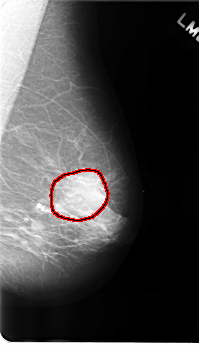

C_0177_1.LEFT_MLO

FILE: C_0177_1.LEFT_MLO.OVERLAY

TOTAL_ABNORMALITIES 1

ABNORMALITY 1

LESION_TYPE MASS SHAPE ROUND MARGINS ILL_DEFINED

ASSESSMENT 4

SUBTLETY 5

PATHOLOGY MALIGNANT

TOTAL_OUTLINES 1

BOUNDARY